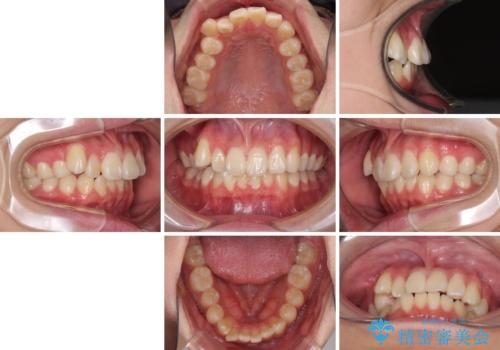

- 八重歯を気にして来院された高校生の患者様です。

ボディーコンタクトの激しい部活動を行っているため、補助装置とインビザラインを用いて、部活動を継続しながら治療を行うこととしました。

八重歯を効率よく改善するため、補助装置を使用して上顎の奥歯を後方に移動させました。

部活動をしながらでしたが、マウスピースをしっかりと装着してくださったので、1年半程度で終了することができました。